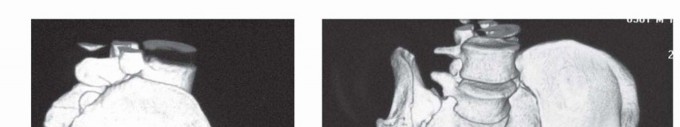

DEFINITION High tibial osteotomy (HTO) is realignment surgery, which has developed for treating medial compar…

DEFINITION Severe deformity is a congenital (acquired or iatrogenic) abnormality in the size and shape of the…